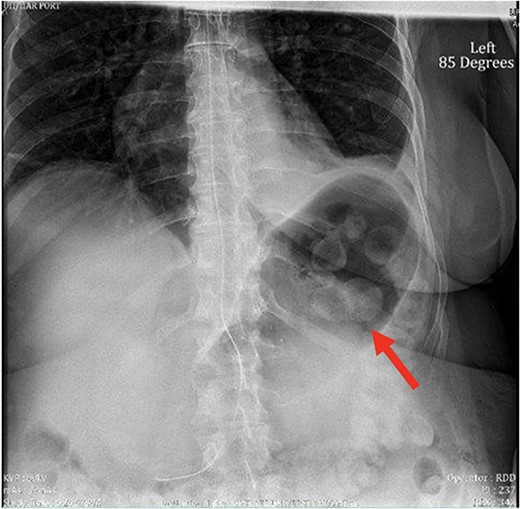

The patient was discharged on the second postoperative day following effective pain management and diet tolerance. However, she presented in the emergency department the following day with uncontrolled pain. Work-up revealed normal white blood cell count, absence of fever, and regular bowel function; she was admitted for pain control and IV hydration. She was not tolerating adequate oral intake. An abdominal X-ray was obtained showing a large gastric bubble, as seen in Fig. 1. The decision was made to place a nasogastric tube (NGT) for gastric decompression.

X-ray image of abdomen confirming persistent large gastric bubble despite adequately positioned NGT.